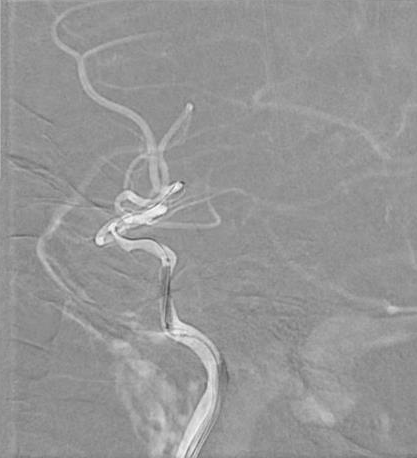

治疗过程

将 6F 导引导管送至 C3 段。

导丝怎么扩【载药时代 球扩天下】NOVA DES®颅内药物洗脱支架在颈内动脉颅内段重度狭窄中的应用体会二例!_https://www.jmylbn.com_新闻资讯_第24张

导引导管到位,导丝通过病变

通过微导丝携带球囊至狭窄段。

导丝怎么扩【载药时代 球扩天下】NOVA DES®颅内药物洗脱支架在颈内动脉颅内段重度狭窄中的应用体会二例!_https://www.jmylbn.com_新闻资讯_第25张

球囊通过病变